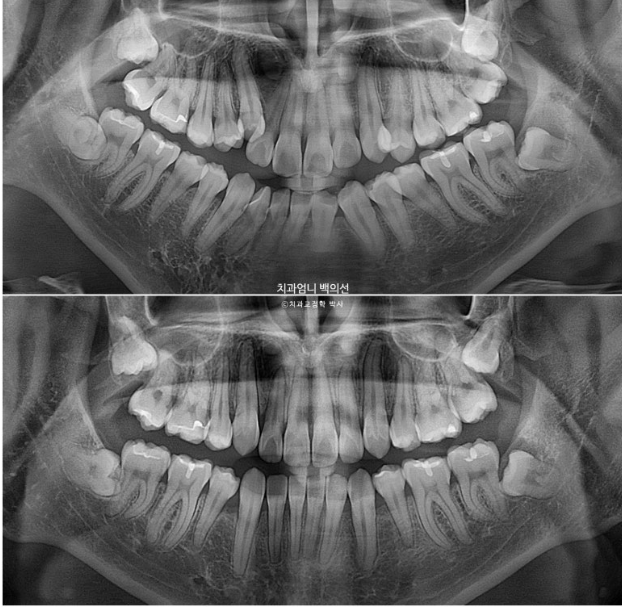

22.09~25.04

재제작은 총 2회 하였으며 치료기간은 2년 6개월 입니다. 중간중간 장치제작기간을 제외하면 실제 치료기간은 2년 2개월 입니다.

치근흡수는 없으며 치근평행도는 양호합니다